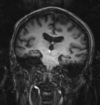

Intra-subject Brain PET-MRI with MRI orientation adjustment

fixed image/target | moving image |

- reference/fixed : baseline MRI:coronal T1w , 256 x 256 x 79, 0.86 x 0.86 x 2.5 mm

- moving: PET: axial, fluorodeoxyglucose, 128 x 128 x 35, 4.29 x 4.29 x 4.25 mm

uncorrected MRI as read from DICOM. Note that image is distorted due to incomplete header information. See the registration challenges section below.